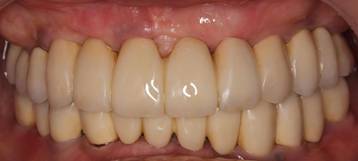

術後。上部構造はハイブリッドレジンです。しっかり嚙めるようになり喜んでいただきました。

上顎

下顎

上部構造装着後6年。ハイブリッドレジンを使用したため、少し艶がなくなってきました。上部構造の材料には金属、ハイブリッドレジン、セラミックなどがあります。セラミックはきれいですが欠けやすいため、最近はフルジルコニアを使っています。

上顎 少しすり減ってきました。

下顎。12か月に一度メインテナンスをしています。

インプラント装着後6年。順調に経過しています。12か月毎のメインテナンスをしています。